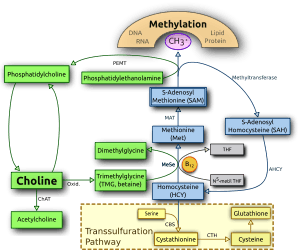

Choline and its metabolites are needed for three main physiological purposes: structural integrity and signaling roles for cell membranes, cholinergic neurotransmission (acetylcholine synthesis), and a major source for methyl groups via its metabolite, trimethylglycine (betaine), which participates in the S-adenosylmethionine (SAMe) synthesis pathways.[14][15]

The human body can produce choline by methylation of phosphatidylethanolamine by N-methyltranferase (PEMT) to form phosphatidylcholine in the liver, or it may be consumed from the diet. It has been demonstrated that both de novo production and dietary consumption are necessary, as humans eating diets lacking choline develop fatty liver, liver damage, and muscle damage. However, because of the close interplay between choline, folate, methionine, and vitamin B12, (whose pathways overlap), the function of choline can be complex.

To begin with, methionine can be formed two ways, either from methyl groups derived from folate, or from methyl groups derived from betaine (which gets its methyl groups from choline). Changes in one of these pathways is compensated for by the other, and if these pathways do not adequately supply methyl groups to produce methionine, the precursor to methionine, homocysteine, rises.

Functions in the fetus

Neural tube closure

While folate is most well known for preventing neural tube nonclosure (the basis for its addition to prenatal vitamins), folate and choline metabolism are interrelated. Both choline and folate (with the help of vitamin B12) can act as methyl donors to homocysteine to form methionine, which can then go on to form SAM (S-Adenosyl methionine) and act as a methyl donor for methylation of DNA. Dietary choline deficiency alone without concurrent folate deficiency can decrease SAM concentration, suggesting that both folate and choline are important sources of methyl groups for SAM production.[57] Inhibition of choline absorption and use is associated with neural-tube defects in mice, and this may also occur in humans.[56] A retrospective case control study (a study that collects data after the fact, from cases occurring without the investigator causing them to occur) of 400 cases and 400 controls indicated that women with the lowest daily choline intake had a four-fold greater risk of having a child with a neural-tube defect than women in the highest quartile of intake.[75]